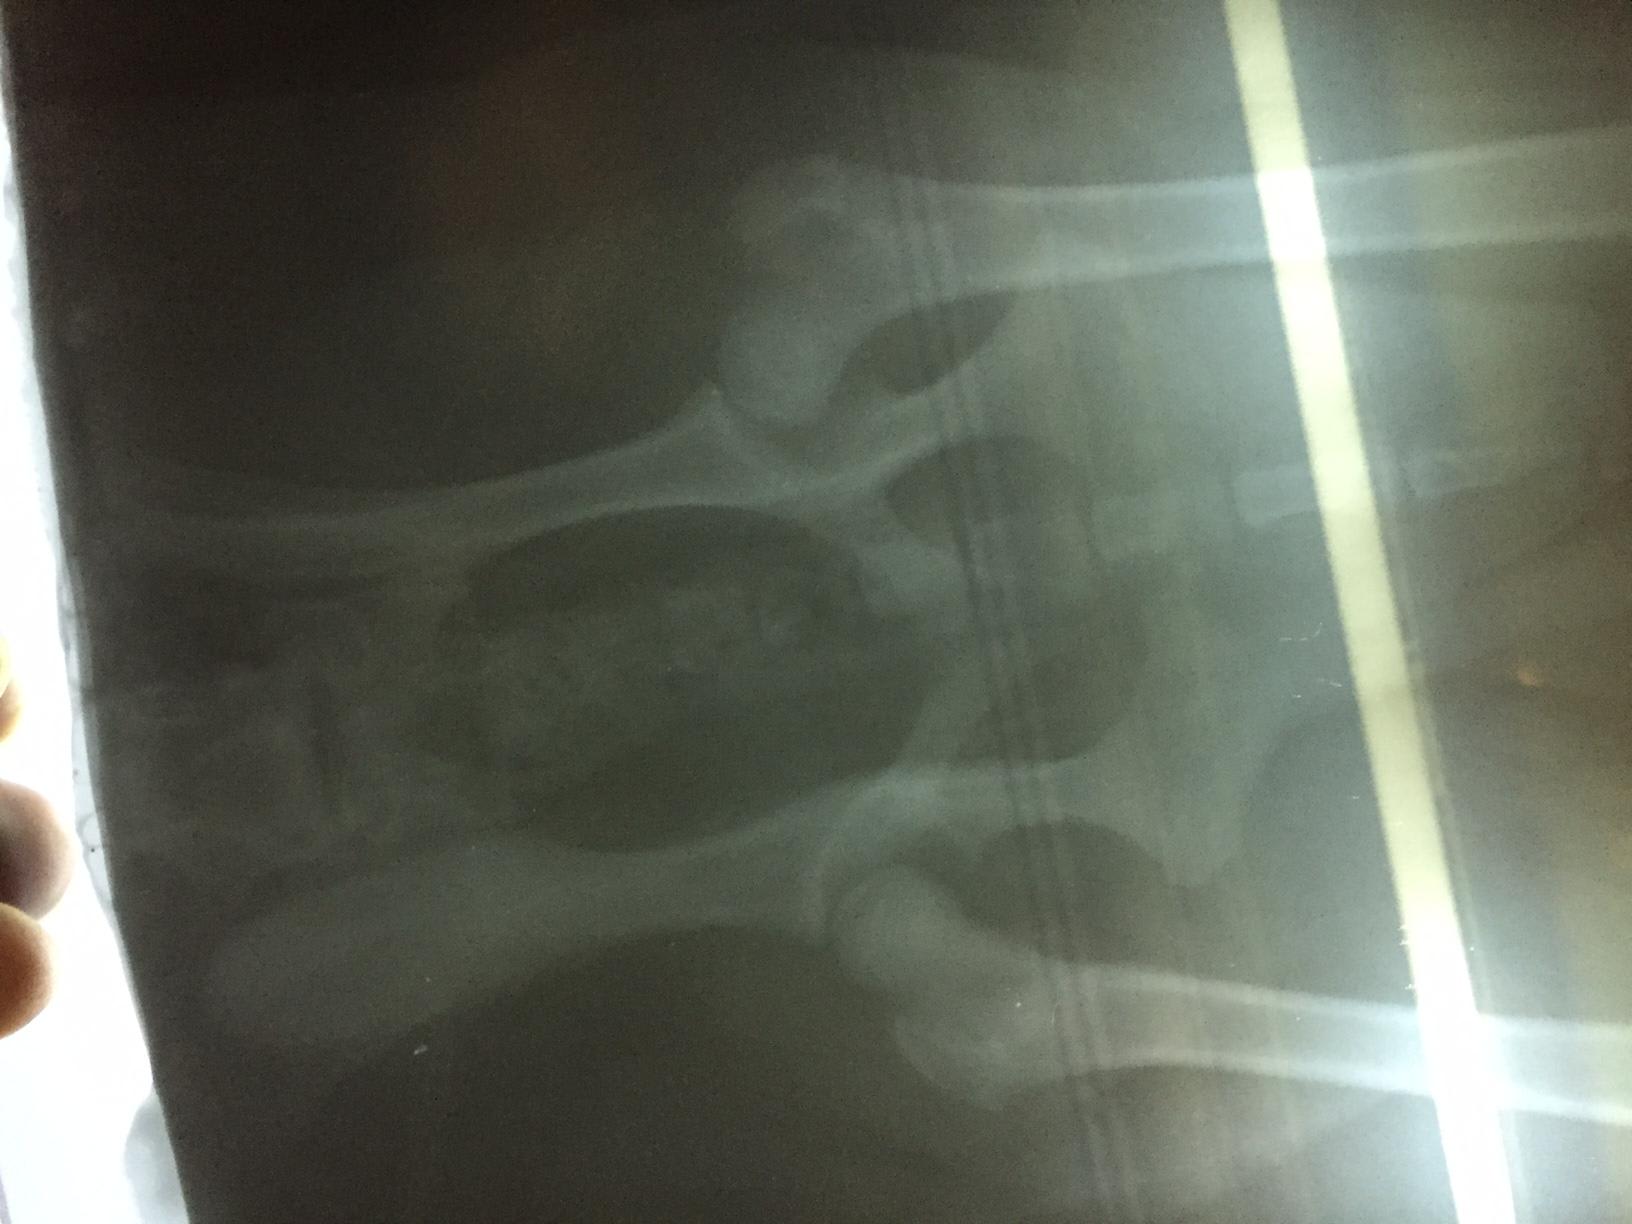

I showed the X-Ray to 2 doctors. One Doctor said that the position of limbs are not good & this issue may be there for life or may be not & the other doctor said that X-Ray hasn't been positioned properly so it looks like joints are sublimated, also he is a pup, so suggested to continue with HD tablets & Pet joint for a month. She also asked me not to overthink until Browny is not able to walk or move. Need one more opinion. Need to understand what does the X-Ray show..

I agree with the doctor who said the x-rays were not positioned properly. In order to obtain really diagnostic quality hip x-rays, the patience should be fully sedated. Without being able to bend the hips all the way downward, you simply can not obtain completely accurate results. Depending on the current clinical picture, I might possible recommend starting medication. Joint supplementation definitely can't hurt, but starting an NSAID at this early of an age is not advisable unless there is clear and obvious discomfort / inflammatory pain. Hope this helps!